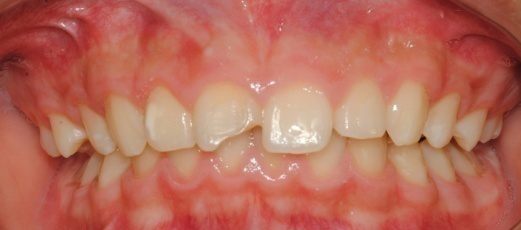

À§ ȯÀÚ´Â À´Ï°¡ ¾Æ·§´Ï¸¦ ³Ê¹« µ¤¾î¿ä(°ú°³±³ÇÕ) ¸¦ ÁÖ¼Ò·Î ³»¿øÇÑ ÃʵîÇлýÀ̾ú½À´Ï´Ù. ÅμºÀå ¾ÇÁ¤ÇüÀåÄ¡ »ç¿ëÈÄ È£ÈíÀÌ °³¼± µÇ¾úÀ¸¸ç Ä¡·áÀü¿¡ ºñÇØ ۰¡ 10cmÁ¤µµ ±Þ¼Ó ¼ºÀåÇÏ¿´½À´Ï´Ù.

°ú°³±³ÇÕ°ú ¹«ÅÎ,ÅΰüÀýÀ» ÁÖ¼Ò·Î ³»¿øÇÏ¿© ÅμºÀå ¾ÇÁ¤ÇüÀåÄ¡¸¦ ÀÌ¿ëÇÏ¿© Ä¡·áÁßÀΠȯÀÚ·Î Ä¡·á½ÃÀÛ½ÃÁ¡ ±âÁØÀ¸·Î ÇöÀç ۰¡ ¾à 8cmÁ¤µµ ¼ºÀåÇÏ¿´½À´Ï´Ù. (Âü°í·Î 2³âÂ÷ ¿©µ¿»ý°ú ۰¡ 7-9cmŰ Â÷À̳²)